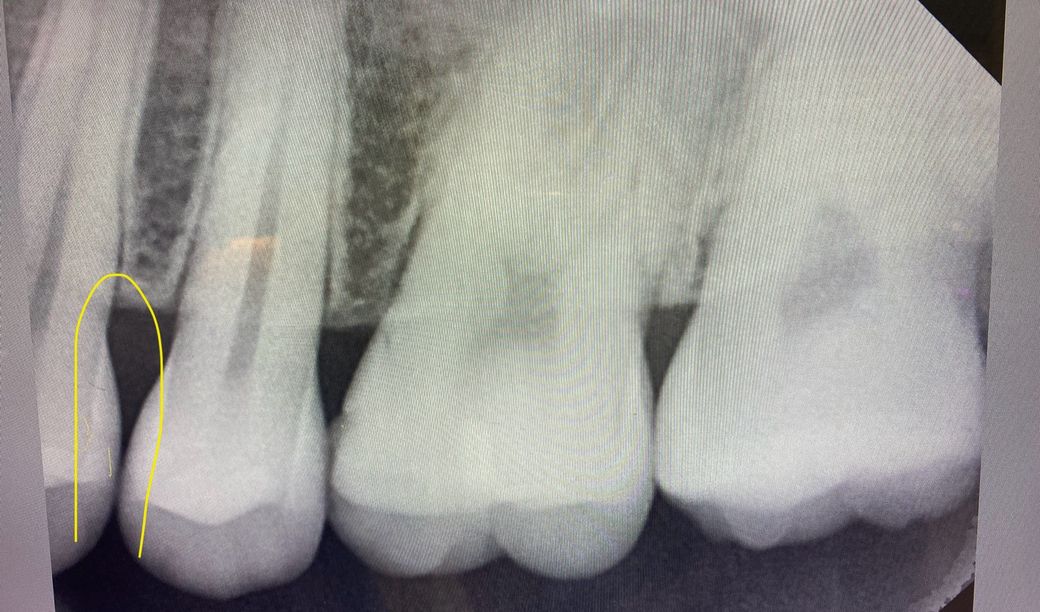

• 3번 째 사진

엑스레이 상으로 치아 사이에 충치가 잇는거 같습니다. 크게 진행된 상태는 아니니 일단 관리를 하시면서 지켜보세요.

2. 아마도, 방사선 사진과 육안 사진이 다른 치아 위치로 보입니다. 확인 해보세요

3. 방사선 사진은 왼쪽 위 작은 어금니 찍은거고, 육안 사진은 오른쪽 위 작은 어금니입니다.